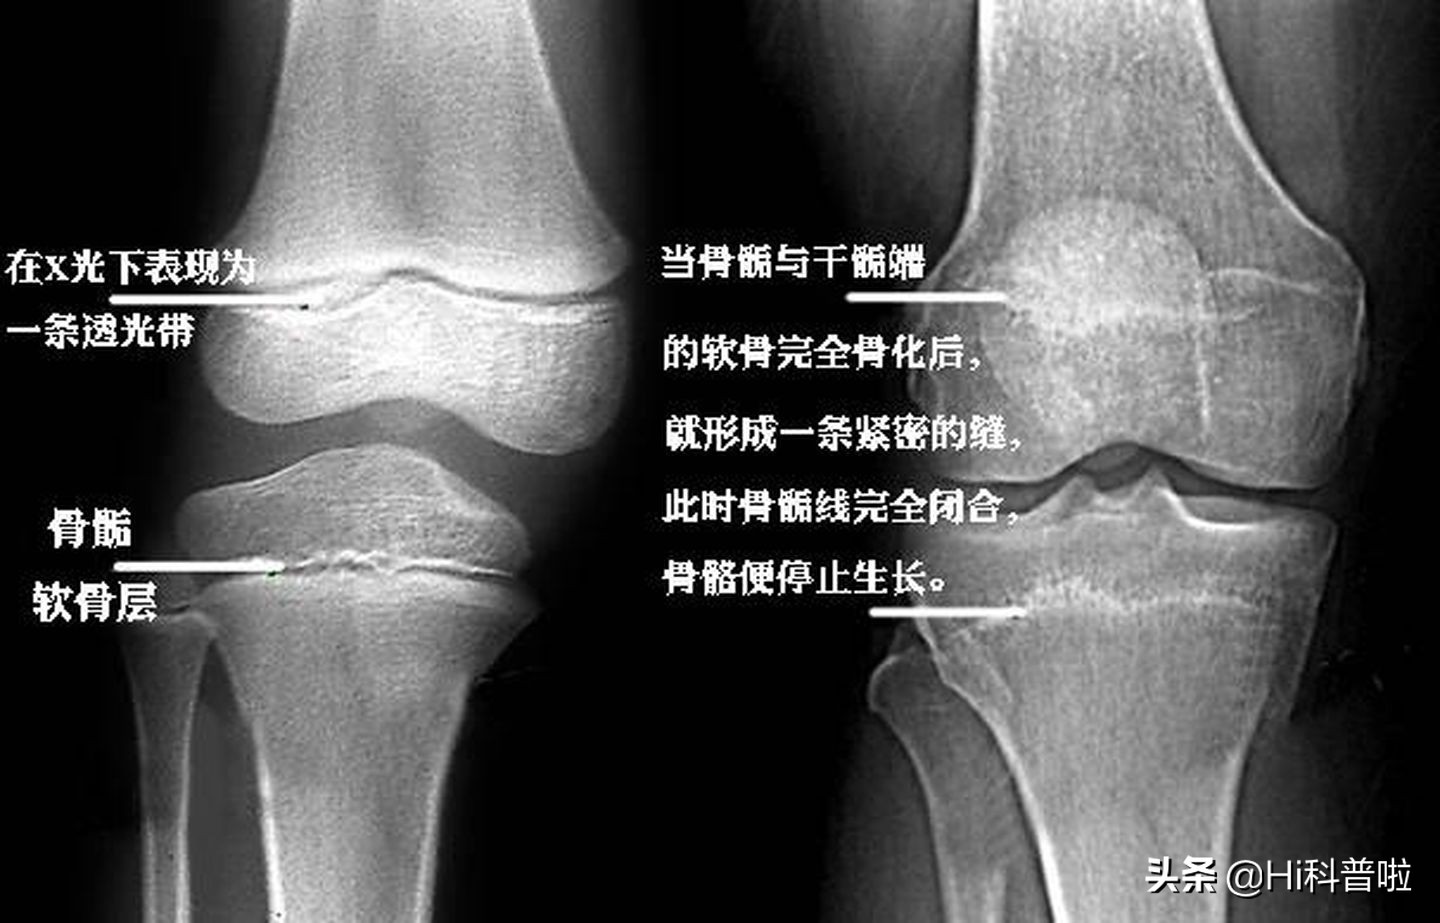

危害一:影响成年身高。由于过早的性发育,在性激素的作用下,身高快速增长,但是同时也会促进骨骺过早闭合,骨骺线一旦闭合,长高的空间基本也消失了。所以性早熟的儿童成年后会比一般人矮。